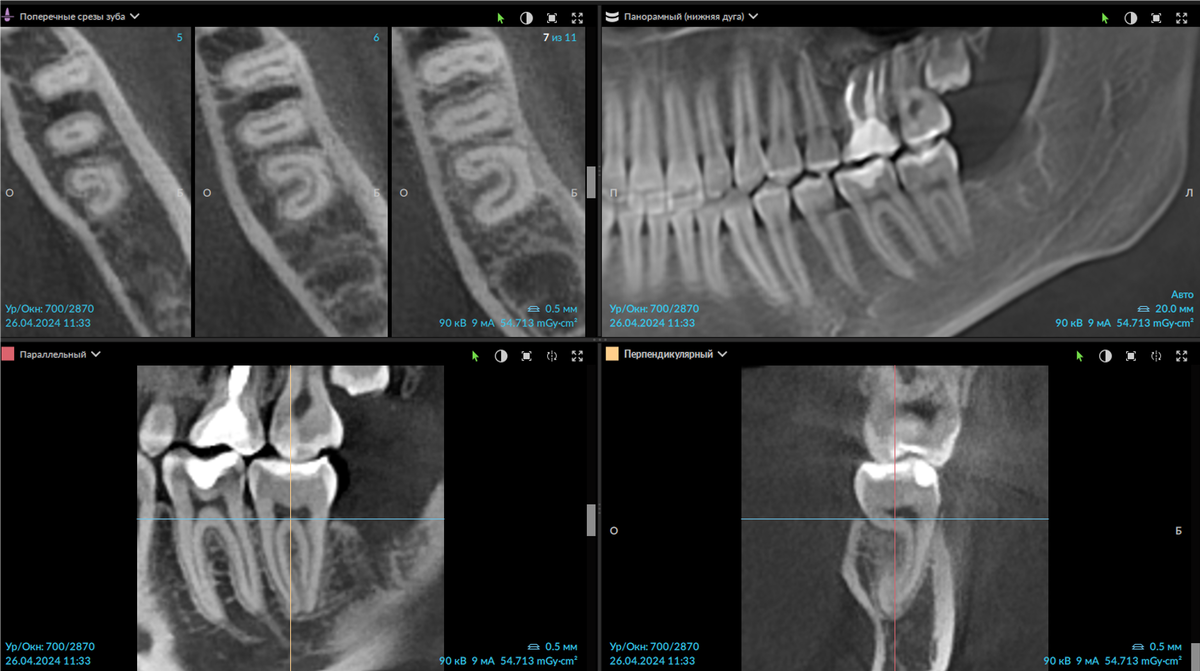

Но имея компьютерную томограмму того же пациента, DTX Studio Clinic помогает выставить в одном окне: все необходимые срезы, эндо-режим, панорамный реформат. Мы видим достаточно нетипичное строение зуба -

С-образный канал.

Пациент женщина, 2003 г.р., зуб 3.7 анатомия